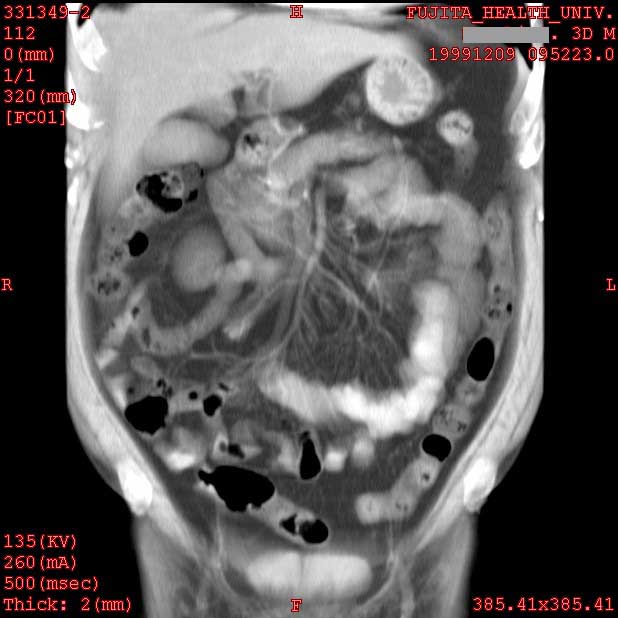

Normal colon and mesenteric arteries

2mmx4, Pitch 5, 150mAs

Ray-sum image

Data acquired by H. Anno M.D., processed by T. Takahara M.D. and K. Katada M.D.